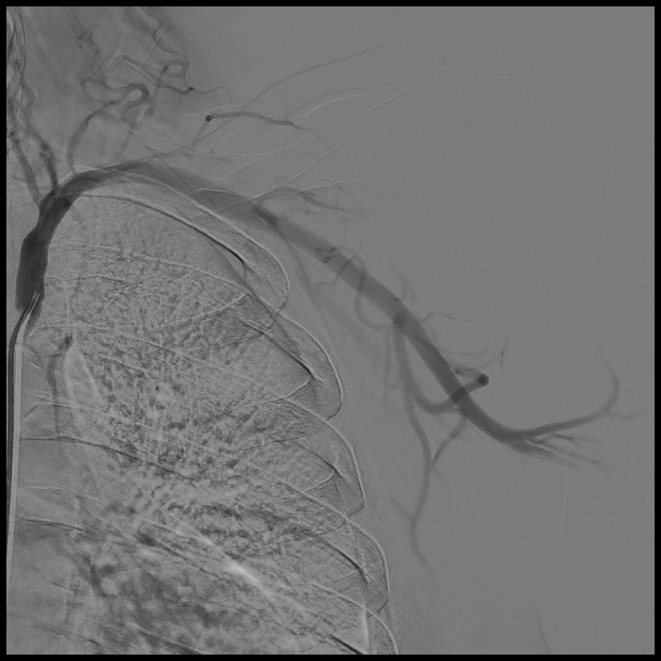

Case presentation: We present a case of incidentally discovered left subclavian stenosis in a 65-year-old male who was admitted for spinal surgery. The patient had a history of peripheral arterial disease, diabetes mellitus, and heavy smoking. During the preoperative assessment, the blood pressure readings in the department were within the normal range. In the operating theater, blood pressure readings of the two arms revealed readings of 136/85 mmHg and 235/114 mmHg in the right and left arms, respectively. Accordingly, the operation was postponed for further evaluation of the increased interarm systolic blood pressure difference. Computed tomography angiography revealed focal stenosis at the origin of the left subclavian artery, causing approximately 90% narrowing. The patient underwent a successful subclavian artery angioplasty.

背景:锁骨下动脉狭窄主要由动脉粥样硬化改变引起,可导致上肢和中枢神经系统发生缺血事件。其他病因包括辐射暴露、血管炎、神经纤维瘤病、外压迫综合征和纤维肌肉发育不良。这些患者的常规麻醉挑战是维持脑灌注。病例介绍:我们报告一例偶然发现左锁骨下狭窄的65岁男性谁是入院脊柱手术。患者有外周动脉疾病、糖尿病和重度吸烟史。术前评估时,科室血压读数在正常范围内。在手术室中,两臂的血压读数显示右臂和左臂分别为136/85 mmHg和235/114 mmHg。因此,手术被推迟,以进一步评估臂间收缩压差的增加。计算机断层血管造影显示左侧锁骨下动脉起源处局灶性狭窄,导致约90%狭窄。患者接受了成功的锁骨下动脉血管成形术。结论:报告有外周动脉疾病、重度吸烟或严重代谢综合征病史的患者的血压读数是很重要的。锁骨下狭窄患者容易出现臂间收缩压差增高。因此,双侧血压测量是一种简单的测试,在紧急情况下对麻醉前评估有重要影响。